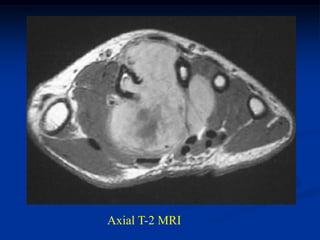

Cor T-1   T-2   Gad

Sag T-1

Gad

Axial T-1   T-2